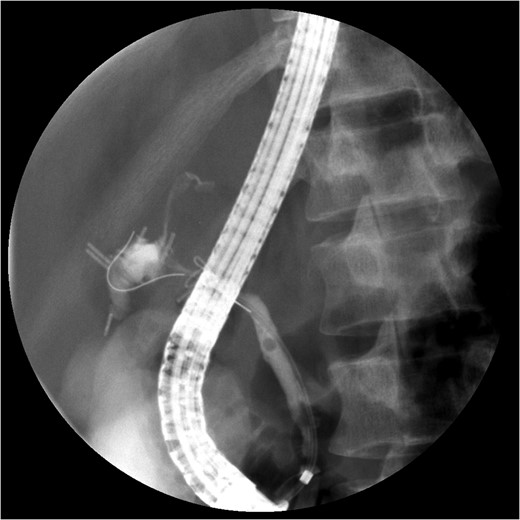

The PTC study confirmed the presence of a completely transected duct, and, fortunately, the ductal injury was traversed with a wire with entry into the distal ductal orifice and into the duodenum (Figs 4–6). Following the procedure, the patient was taken directly to the operating room for open surgical repair.

Percutaneous Transhepatic Cholangiogram showing contrast filling the distal duct following continued injection.